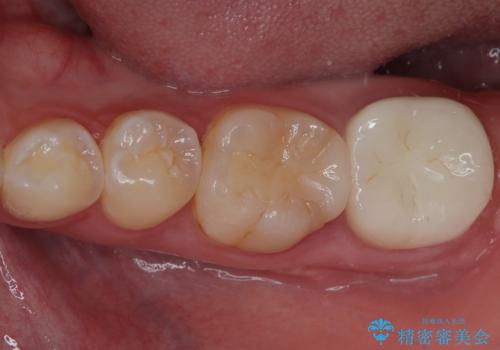

下顎大臼歯の再根管治療とオールセラミッククラウンによる補綴治療